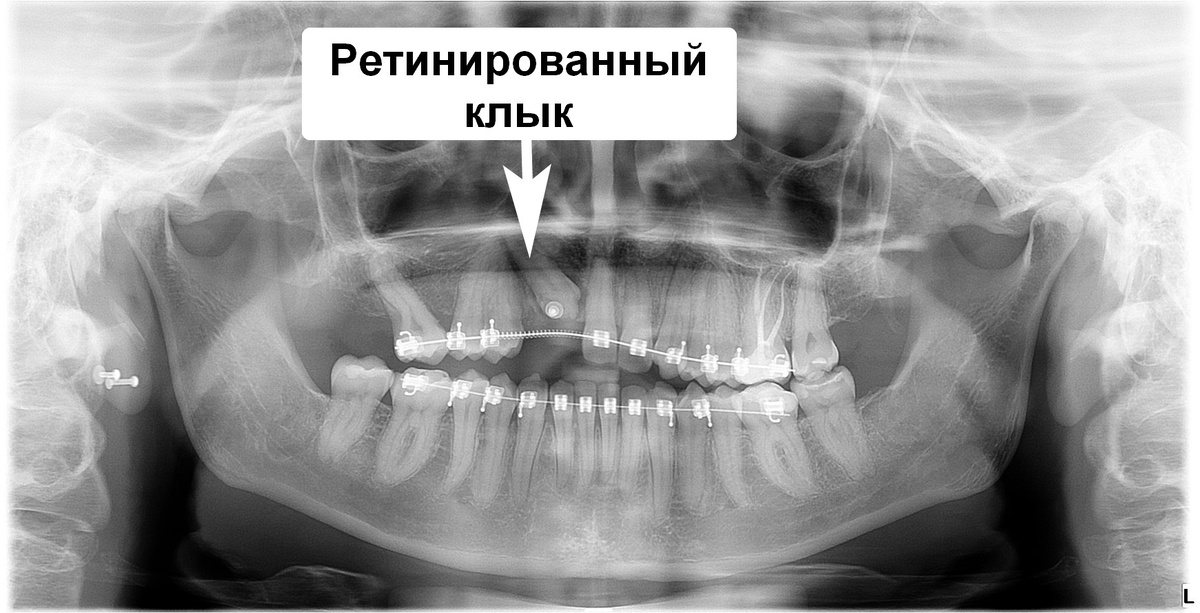

История пациента: как брекетами вытянуть ретинированный клык

Клык не прорезался и находится в толще костной ткани верхней челюсти

Клык на верхней челюсти справа (зуб 1.3) ретинирован и полностью находится в кости челюсти

Адентия боковых резцов (это зубы 1.2 и 2.2), их не было с рождения